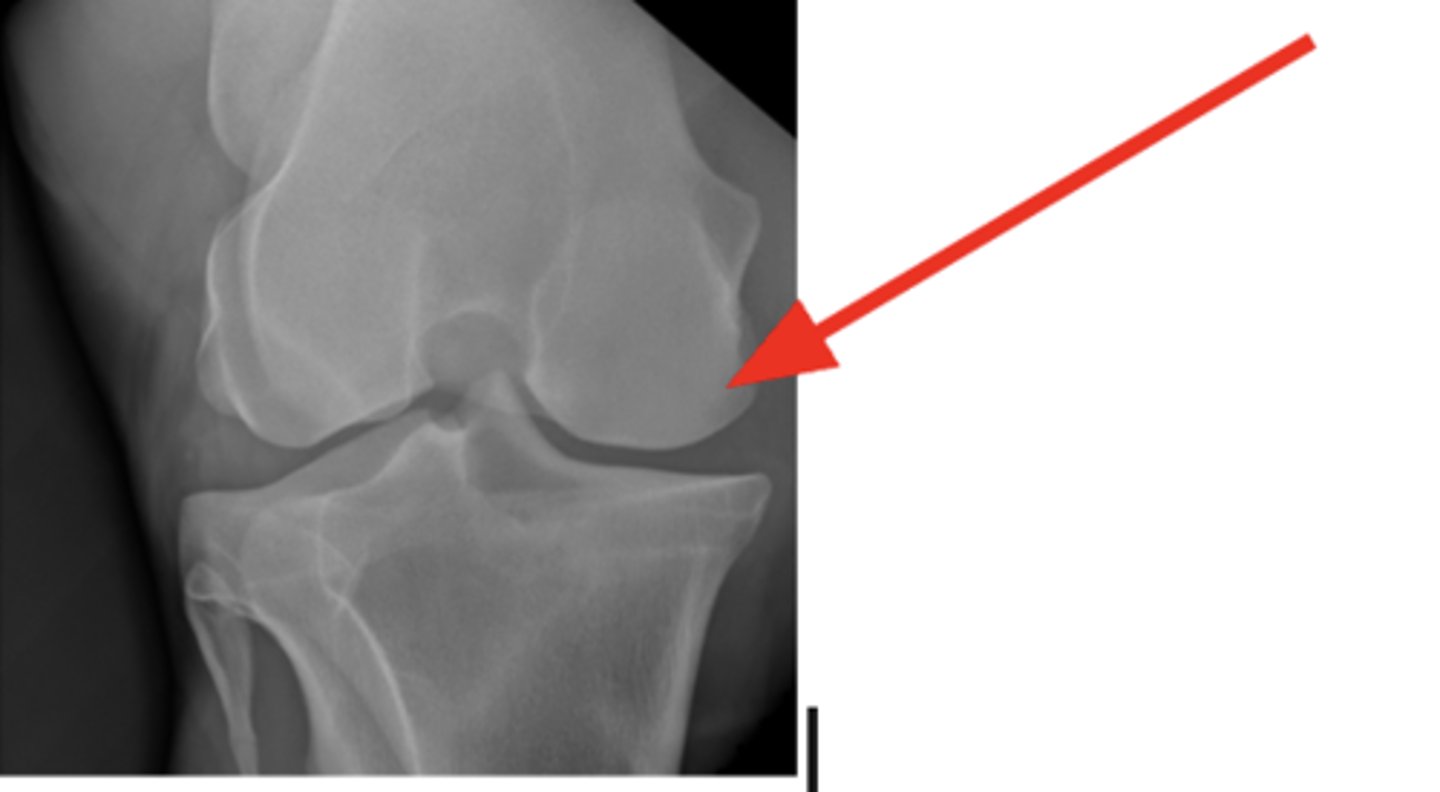

Medial femoral epicondyle

3 y/o horse lameness, effusion of stifle, where is the cyst?